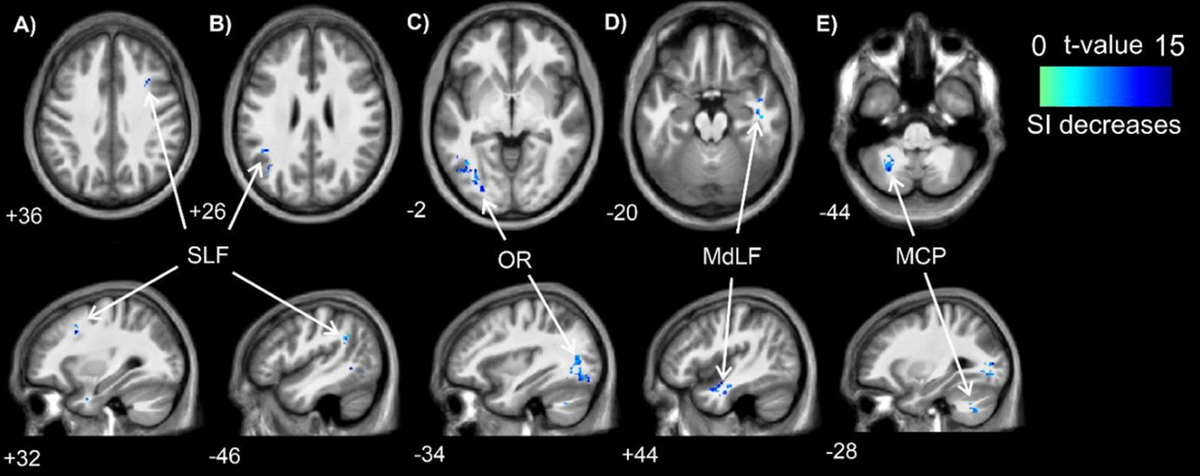

Результаты показали изменения в моторной коре — зоне, отвечающей за координацию, — а именно снижение проводимости в белом веществе. Это значит, что мозг тратит больше энергии на обработку информации после ударов.